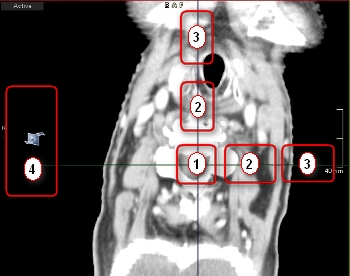

Η προεπιλεγμένη διάταξη MPR αποτελείται από τρία χρωματικά κωδικοποιημένα παράθυρα που εμφανίζουν εγκάρσια, στεφανιαία και οβελιαία επίπεδα. Κάθε ένα από αυτά τα παράθυρα περιέχει δύο τεμνόμενες γραμμές εντοπισμού που αντιπροσωπεύουν τα επίπεδα που είναι ορατά στα δύο άλλα παράθυρα. Οι γραμμές εντοπισμού είναι επίσης χρωματικά κωδικοποιημένες για να αντιστοιχούν στις προβολές που αντιπροσωπεύουν.

| Μετατόπιση κέντρου (1) | Μετακινήστε τη θέση δύο επιπέδων ταυτόχρονα σύροντας τη λαβή μετατόπισης κέντρου. |

| Μετατόπιση επιπέδου (2) | Μετακινήστε τη θέση ενός επιπέδου σύροντας τη λαβή μετατόπισης επιπέδου. |

| Περιστροφή επιπέδου (3) | Περιστρέψτε το επίπεδο (το ορθογώνιο επίπεδο επιστρέφεται επίσης) σύροντας τη λαβή περιστροφής επιπέδου. |

| Λεπτομερής πλοήγηση (4) | Περιηγηθείτε στον όγκο που έχει υποστεί ανασύνθεση σύροντας την περιοχή ενδιαφέροντος λεπτομερούς πλοήγησης. |